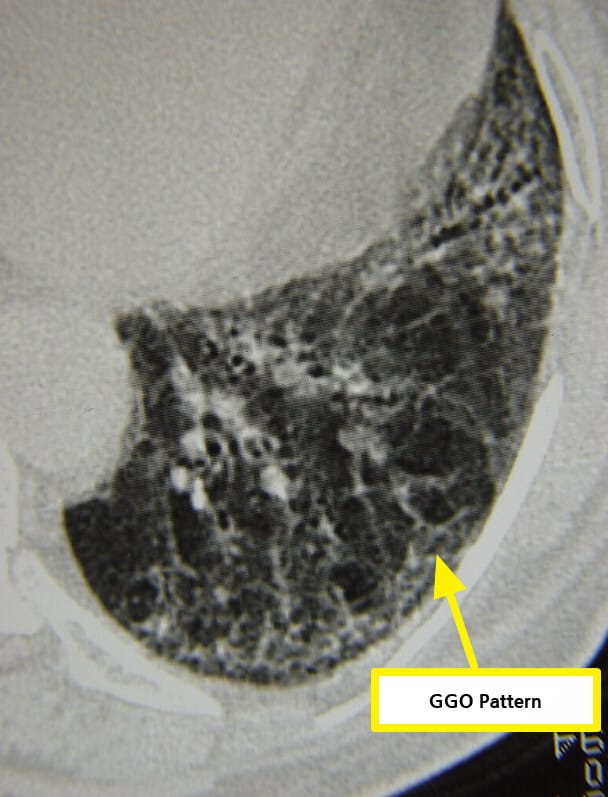

| 🟨 폐섬유화 (Interstitial lung disease) |

| 호흡곤란, 마른기침을 유발하며, 고해상도 CT에서 망상 음영이 관찰됩니다. |

| 🔵 폐 기능 검사 및 HRCT |

| 폐확산능(DLCO) 감소 및 HRCT에서 폐섬유화 확인 시 진단에 도움됩니다. |